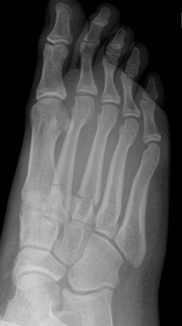

Single and multiple non-displaced metatarsal fractures

Single non-displaced metatarsal fracture     Multiple non-displaced metatarsal fractures

• Follow up Orthopaedic fracture clinic in 7 - 10 days.